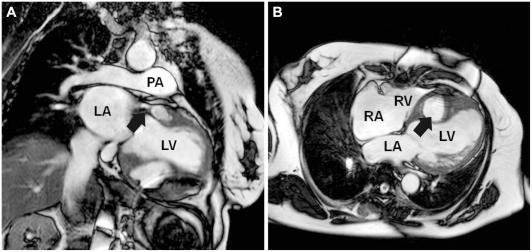

Aneurysm of sinus of valsalva dissecting into the interventricular septum after aortic valve replacement: diagnosis by echocardiography and magnetic resonance imaging and treatment with surgical sealant.

Aneurysm of the sinus of Valsalva that causes dissection of the interventricular septum is an extremely rare entity. In this report we describe a case of aneurysm of the sinus of Valsalva dissecting into the interventricular septum, from the base to mid septum, after aortic valve replacement. After the diagnosis was made by transthoracic echocardiography and magnetic resonance imaging, the patient was successfully treated with surgical sealant-mediated occlusion of the aneurysmal sac and cardiac resynchronization therapy used for the first time.